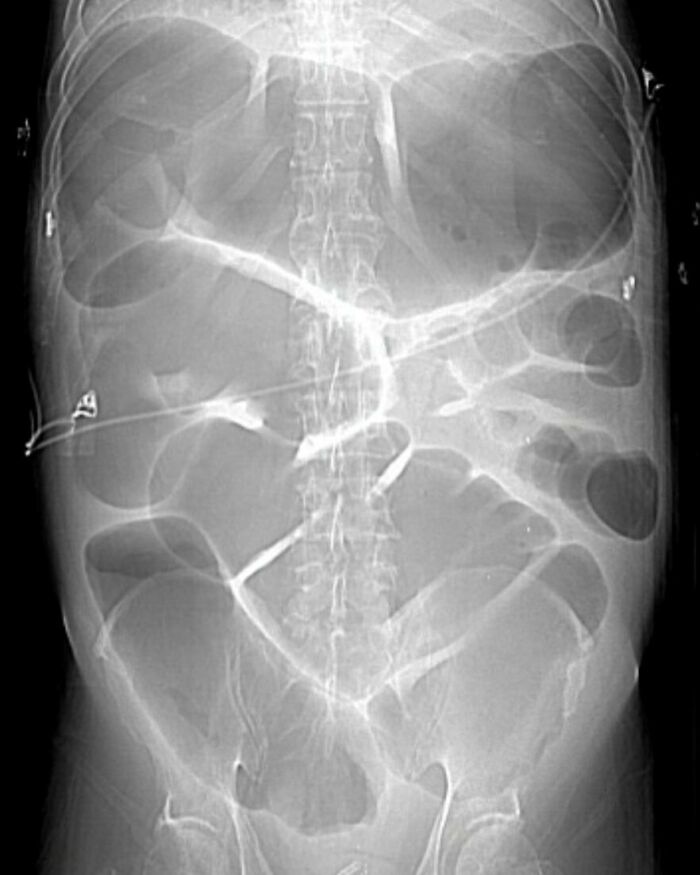

#56

Body riddled with parasites as a result of eating raw pork for 10 years.

Trichinellosis, more commonly known as trichinosis, is a parasitic food-borne disease that is caused by eating raw or undercooked meats, particularly pork products infested with the larvae of a type of roundworm called Trichinella.

When a human or animal eats meat that contains infective Trichinella larvae, the acid in the stomach dissolves the hard covering of the cyst around the larvae and releases the worms. The worms pass into the small intestine and, in 1–2 days, become mature. After mating, adult females lay eggs. Eggs develop into immature worms, travel through the arteries, and are transported to muscles. Within the muscles, the worms curl into a ball and encyst (become enclosed in a capsule). The life cycle repeats when meat containing these encysted worms is consumed by another human or animal.